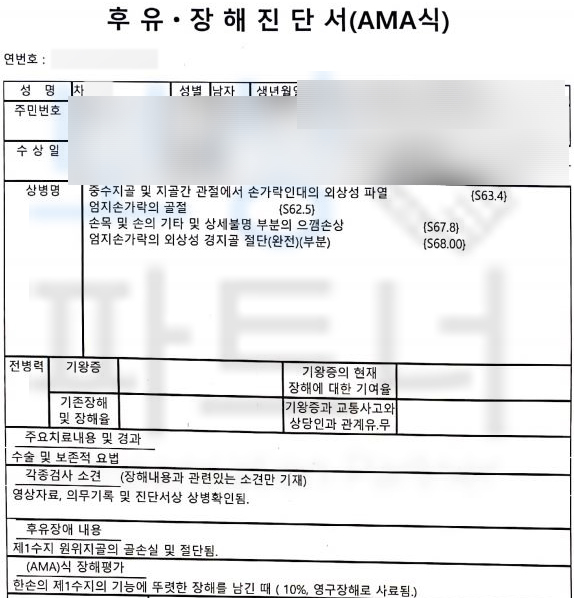

엄지손가락이 분쇄 골절의 형태로 골절되는 사고를 당하셨습니다. 아래의 사진은 사고 당시 엑스선 사진입니다.

위 사고로 차@@님은 엄지손가락에 핀고정을 하는 금속 고정술을 받게 되셨고 다행히도 엄지손가락의 형태가 유지되어 잘 수술을 받으셨습니다.

장해급여는 주치의의 장해 소견서가 필요한데 대부분의 주치의는 자신이 치료한 환자에게 장해 진단을 내리기 쉽지 않을뿐더러 공단에서의 조사 과정도 있기 때문에 쉽지 않죠. 하지만 차@@님은 보상 파트너에 상주하는 노무직원을 통해 산재 장해급여 청구를 위임해 주셨고 산재 장해판정을 함께 진행한 결과

산재 장해등급 13급!!** 일시금 99일**의 총 장해급여 5,544,297원입니다. 보험사에 후유장해보험금 청구를 위해서는 의료 전문의의 후유 장해 진단서가 필요합니다.

저희는 공신력 있는 대학병원의 전문의를 통해 후유 장해 평가를 진행하였고 이를 기초로 작성한 손해사정서와 각종 서류를 각 보험사에 송부하였습니다.

물론 보험사의 내부 자문을 거치며 약 1달간의 시간이 소요되었지만 결국 저희가 처음 청구한 제1수지 뚜렷한 기능장해 인정되어